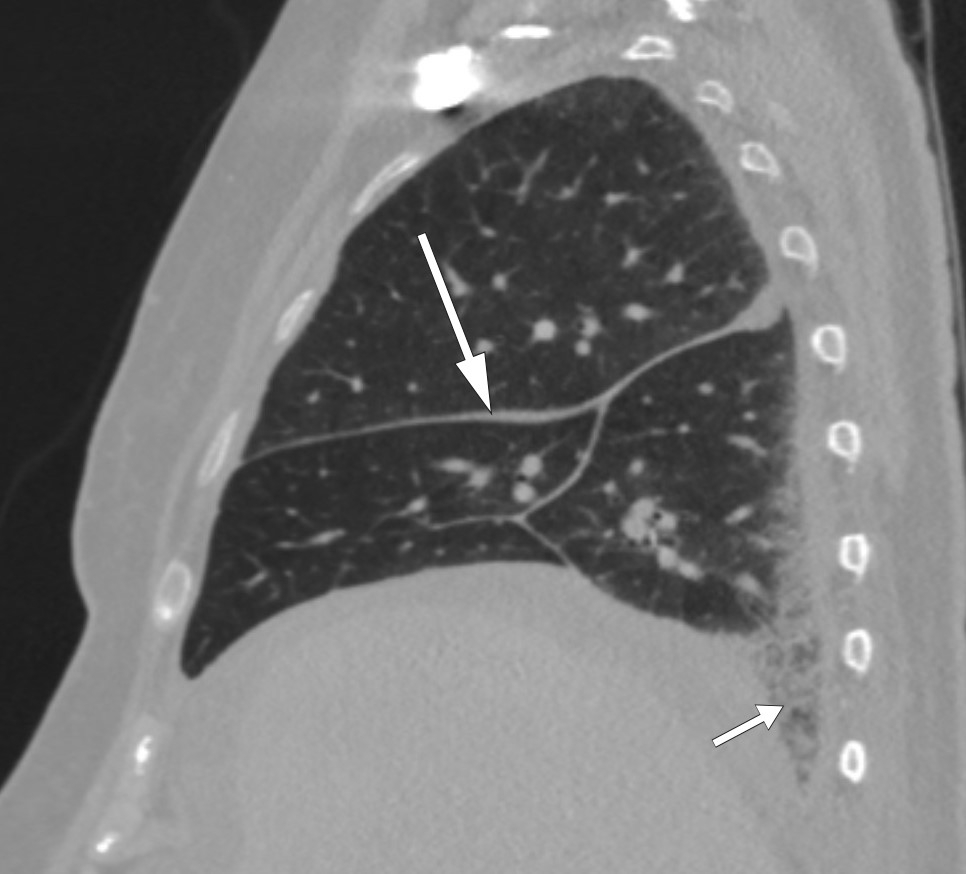

I tillegg til de perinefriske forandringene var det påfallende funn på CT thorax (fig 2) og helkroppsscintigrafi (fig 3). Som et bifunn ble det også funnet en liten lungeembolus. MR hjerte og ekkokardiografi påviste lokalt fortykket perikard, mens MR caput og orbita viste normale funn. Abdominal paracentese viste CD68-positive og CD1a-negative makrofager og ingen tegn til mikrober. I ascitesvæsken, som var gjennomskinnelig og gul, var albuminnivået 13 g/l og proteinkonsentrasjonen 24 g/l (under 30 g/l tydet på transudat). Serum-ascites-albumin-gradienten (SAAG) var 9 g/l, forenlig med at årsaken til ascites ikke var portal hypertensjon. Leukocytter i ascitesvæsken var 0,20 · 109/l, noe som utelukket spontan bakteriell peritonitt. På blodutstryk var det granulocytose og trombocytose, mens benmargsutstryk viste reaktiv/normal benmarg. Benmargsbiopsi viste noen svakt reaktive megakaryocytter, og biopsier fra femur påviste kun osteomyelosklerose. Biopsi fra perinefrisk vev viste fibrose og histiocytter som var positive for CD68 og negative for CD1a, samt en uspesifikk reaksjon for S100-proteiner. Genetisk testing for BRAF-mutasjon var negativ.

Diagnosen Erdheim-Chesters sykdom er basert på kliniske, radiologiske og histologiske funn. Det vanligste er affeksjon av skjelettet, sentralnervesystemet, nyrene og det kardiovaskulære systemet (24, 25). Infiltrasjon i orbita er også beskrevet, for eksempel i en kasuistikk i Tidsskriftet fra 2014 (26). Symptomene avhenger av organaffeksjon, men det typiske er skjelett- eller leddsmerter, dyspné, hoste, eksoftalmus eller xantomer samt synsforstyrrelser, ataksi, hodepine eller andre nevrologiske symptomer. Kardial affeksjon er ofte asymptomatisk, men det kan ha store konsekvenser. Perikardsykdom som perikarditt, perikardvæske eller tamponade rammer opp mot 45 % av pasientene. Det er mer uvanlig med histiocyttinfiltrasjon i myokard og koronarkar, som kan føre til iskemi, klaffefeil eller ledningsforstyrrelser (27). Vår pasient hadde fortykket perikard, visualisert både på CT thorax, MR hjerte og ekkokardiografi, men ingen perikardvæske og god hjertefunksjon for øvrig.